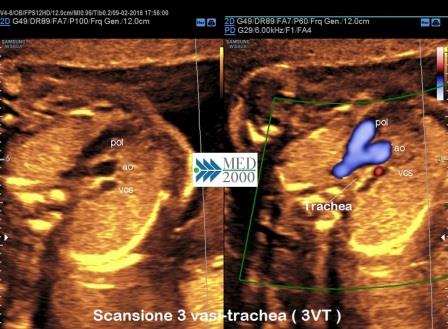

Il decorso normale dell'arco aortico può essere facilmente evidenziato nella scansione 3-vasi-trachea (3VT). Tale scansione è rappresentata da una struttura a V con apice rivolto posteriormente; la branca destra della V è rappresentata dall'arco aortico, la branca sinistra è rappresentata dalla diramazione sinistra dell'arteria polmonare che si continua col dotto arterioso congiungendosi poi all'aorta formando l'apice della V; in questa scansione a destra dell'apice della V vi è la trachea e l'arco aortico è quindi posto a sinistra della trachea.

In ecografia prenatale l'arco aortico viene definito destro o sinistro a seconda se decorre a destra o a sinistra della trachea.